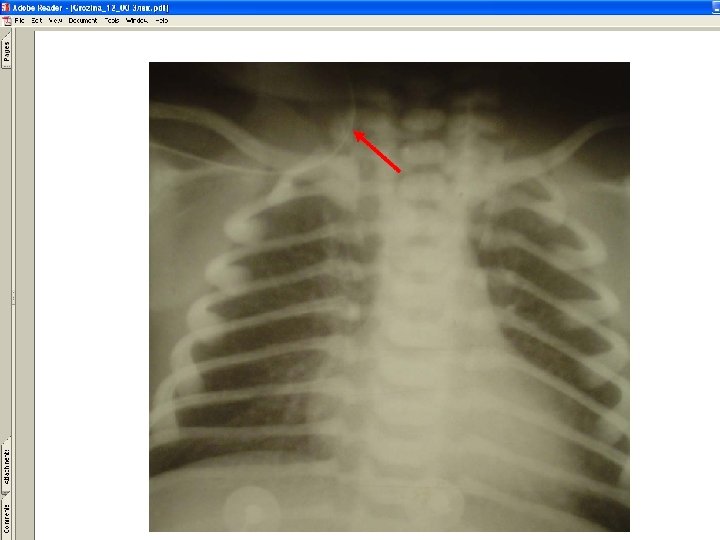

• Types of catheter malposition